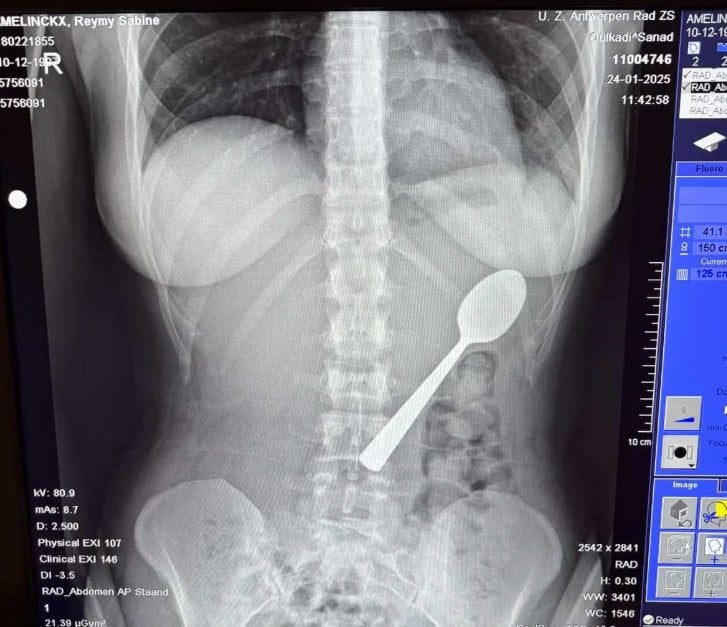

28-летняя бельгийка Рэйми Амелинкс случайно проглотила 17-сантиметровую ложку из-за того, что на нее во время употребления йогурта напрыгнула ее собака. Но девушка сохранила это в секрете, пока не поняла серьезность ситуации.

Женщина рассказала, что почувствовала, как ложка плавно скользит в желудок, и ей пришлось выбрать между тем, чтобы задохнуться или проглотить ее полностью. Сначала Рейми пыталась достать ложку рукой, но события развивались слишком быстро. Девушка скрыла инцидент от своего парня до вечера.

Когда поняла серьезность ситуации, женщина обратилась к врачам. Специалисты сказали, что ложка слишком велика для природного прохождения, поэтому пришлось проводить гастроскопию под местной анестезией. Во время процедуры ложку вращали в желудке, что повлекло за собой небольшое желудочное кровотечение, но удалось избежать хирургического вмешательства.

«Однако я все же завоевала репутацию «той девушки с ложкой» на всю жизнь. На следующий день я вернулась к работе, как обычно. Мои коллеги не поверили мне, пока я не показала им рентгеновский снимок», – делится потерпевшая.